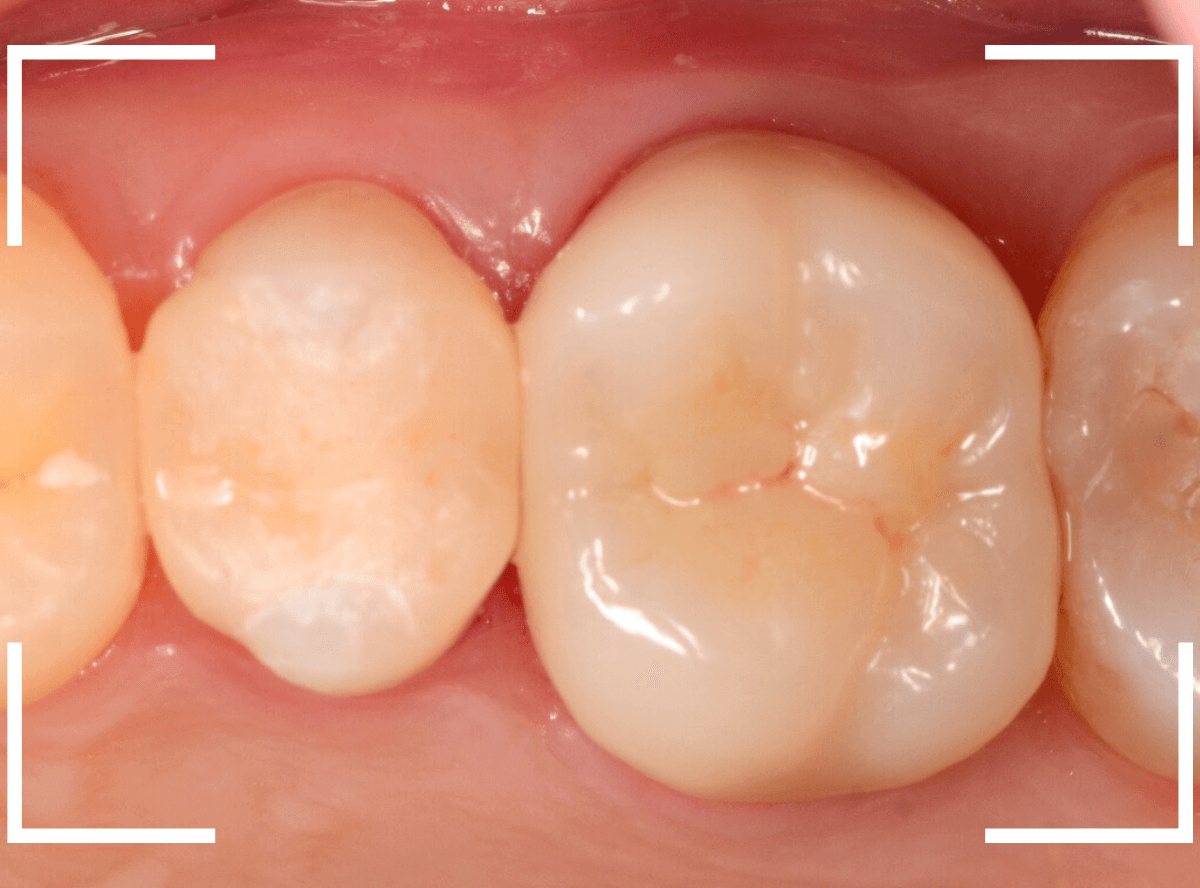

治療前後の比較です。

比べてみると、白い歯の良さがわかると思います。

患者さんにも、喜んでいただき、いつもながらほっとしました。